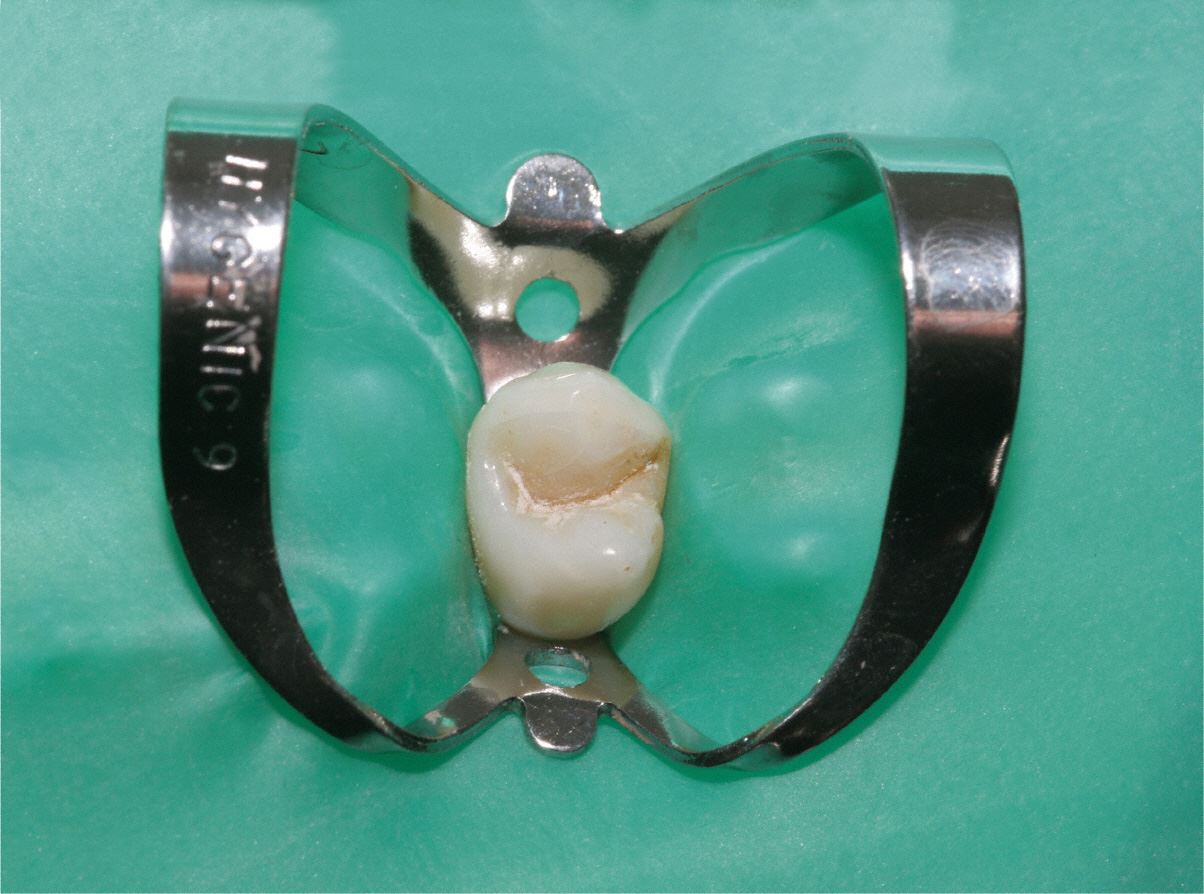

Kofferdam

Für eine effiziente Wurzelbehandlung müssen Bakterien restlos aus dem Wurzelkanal beseitigt werden.

Dafür benutzt man einen speziellen Spanngummi, genannt "Kofferdam", der sowohl den Zahn isoliert, als auch das Eindringen von Bakterien aus der Mundhöhle in den Zahn verhindert. Gleichzeitig wird vermieden, dass der Patient kleine Instrumente oder Materialien verschluckt.